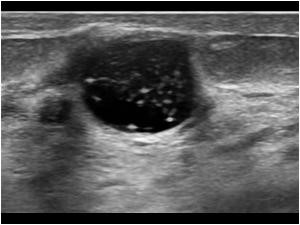

Сложные кисты обязательно подвергаются инвазивным методам диагностики с цитологическим или гистологическим исследованием материала. Вероятность озлокачествления сложной кисты равна 0.3%. При выявлениях сложных кист хирургическая тактика предлагается более активно.

сложная киста молочной железы.

В настоящее время в СПб больнице РАН мы можем предложить безоперационные способы удаления сложных кист молочных желез, методом ваккуумно-аспирационной резекции.